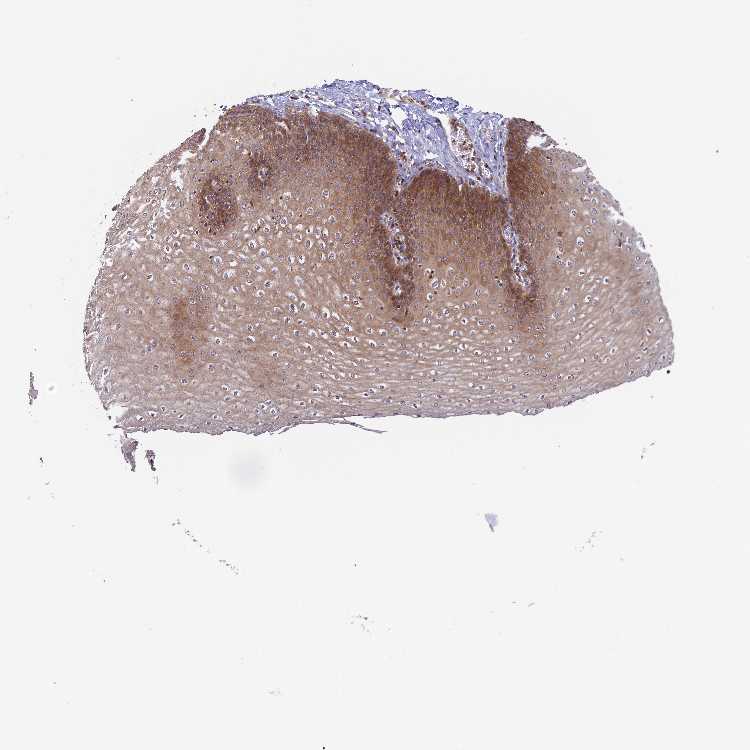

ESOPHAGUS - Antibody stainingi

Antibody staining in the annotated cell types in the current human tissue is reported as not detected, low, medium, or high, based on conventional immunohistochemistry profiling in selected tissues. This score is based on the combination of the staining intensity and fraction of stained cells.

Each image is clickable and will lead to virtual microscopy that enables deeper exploration of all samples and also displays staining intensity scores, fraction scores and subcellular localization as well as patient and tissue information for each sample.

Antibody HPA040983Antibody HPA056548Antibody CAB009110

Squamous epithelial cells MediumMediumNot detected